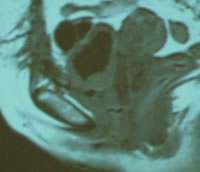

Оценка

результатов лечени. ЯМР - томография. Кольпопексия,

влагалищный лоскут.

До операции

После операции |